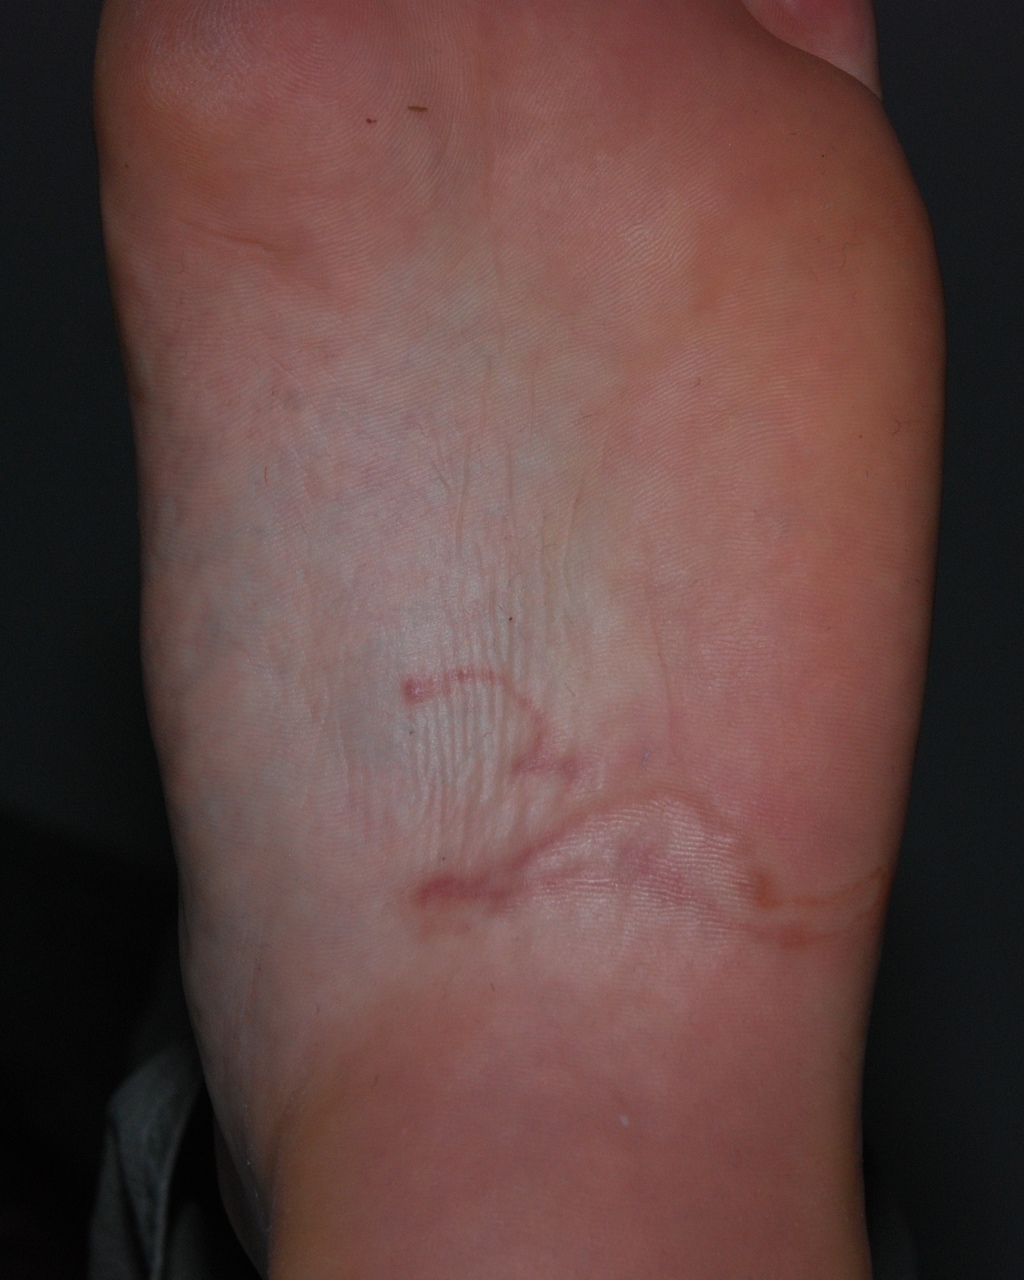

Un sillon serpigineux

Chez l’Homme, les larves traversent l’épiderme à l’endroit du contact cutané avec le sol (pieds, fesses, dos), mais elles ne peuvent pas évoluer et se trouvent en « impasse parasitaire ». Elles migrent alors sur place en creusant des sillons sous ­l’épiderme, puis meurent en quelques ­semaines. Les patients se plaignent de ­cordons sous-cutanés de plusieurs centimètres de long, sinueux, érythémateux et prurigineux, surtout le soir et la nuit. Un ou plusieurs cordons sont observés, en fonction du nombre de larves qui ont traversé la peau (fig. 1 et 2). Ces cordons se modifient chaque jour en raison de la progression des larves de quelques millimètres par jour et se couvrent de vésicules. Le prurit est parfois très intense, provoquant une impétiginisation locale. L’évolution est favorable, avec la disparition des lésions et du prurit en quelques semaines du fait de la mort spontanée des larves. Ces parasitoses cutanées concernent surtout les enfants jouant dans un terrain humide, les baigneurs s’allongeant directement sur le sable et les personnes en contact permanent avec des chiens.2